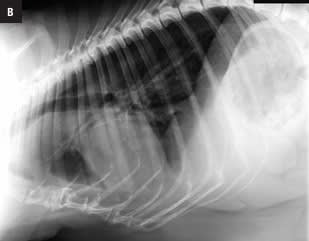

Este atlas de consulta rápida ayudará al clí­nico a obtener la máxima información de sus estudios radiográficos del tórax. Presenta gran cantidad de imágenes que guiarán al veterinario en su interpretación radiográfica, desde la misma técnica, la posición más idónea según la patologí­a que se sospeche o el estado clí­nico del paciente, o variaciones fisiológicas, hasta el órgano o estructuras torácicas a evaluar. Presenta montajes anatómico-radiográficos para ayudar a visualizar las estructuras que se están valorando en la radiografí­a. Aporta imágenes de las proyecciones radiográficas torácicas normales de más de 30 razas caninas para su comparación directa lo que hacen de este libro una guí­a de referencia de radiografí­as torácicas raciales.